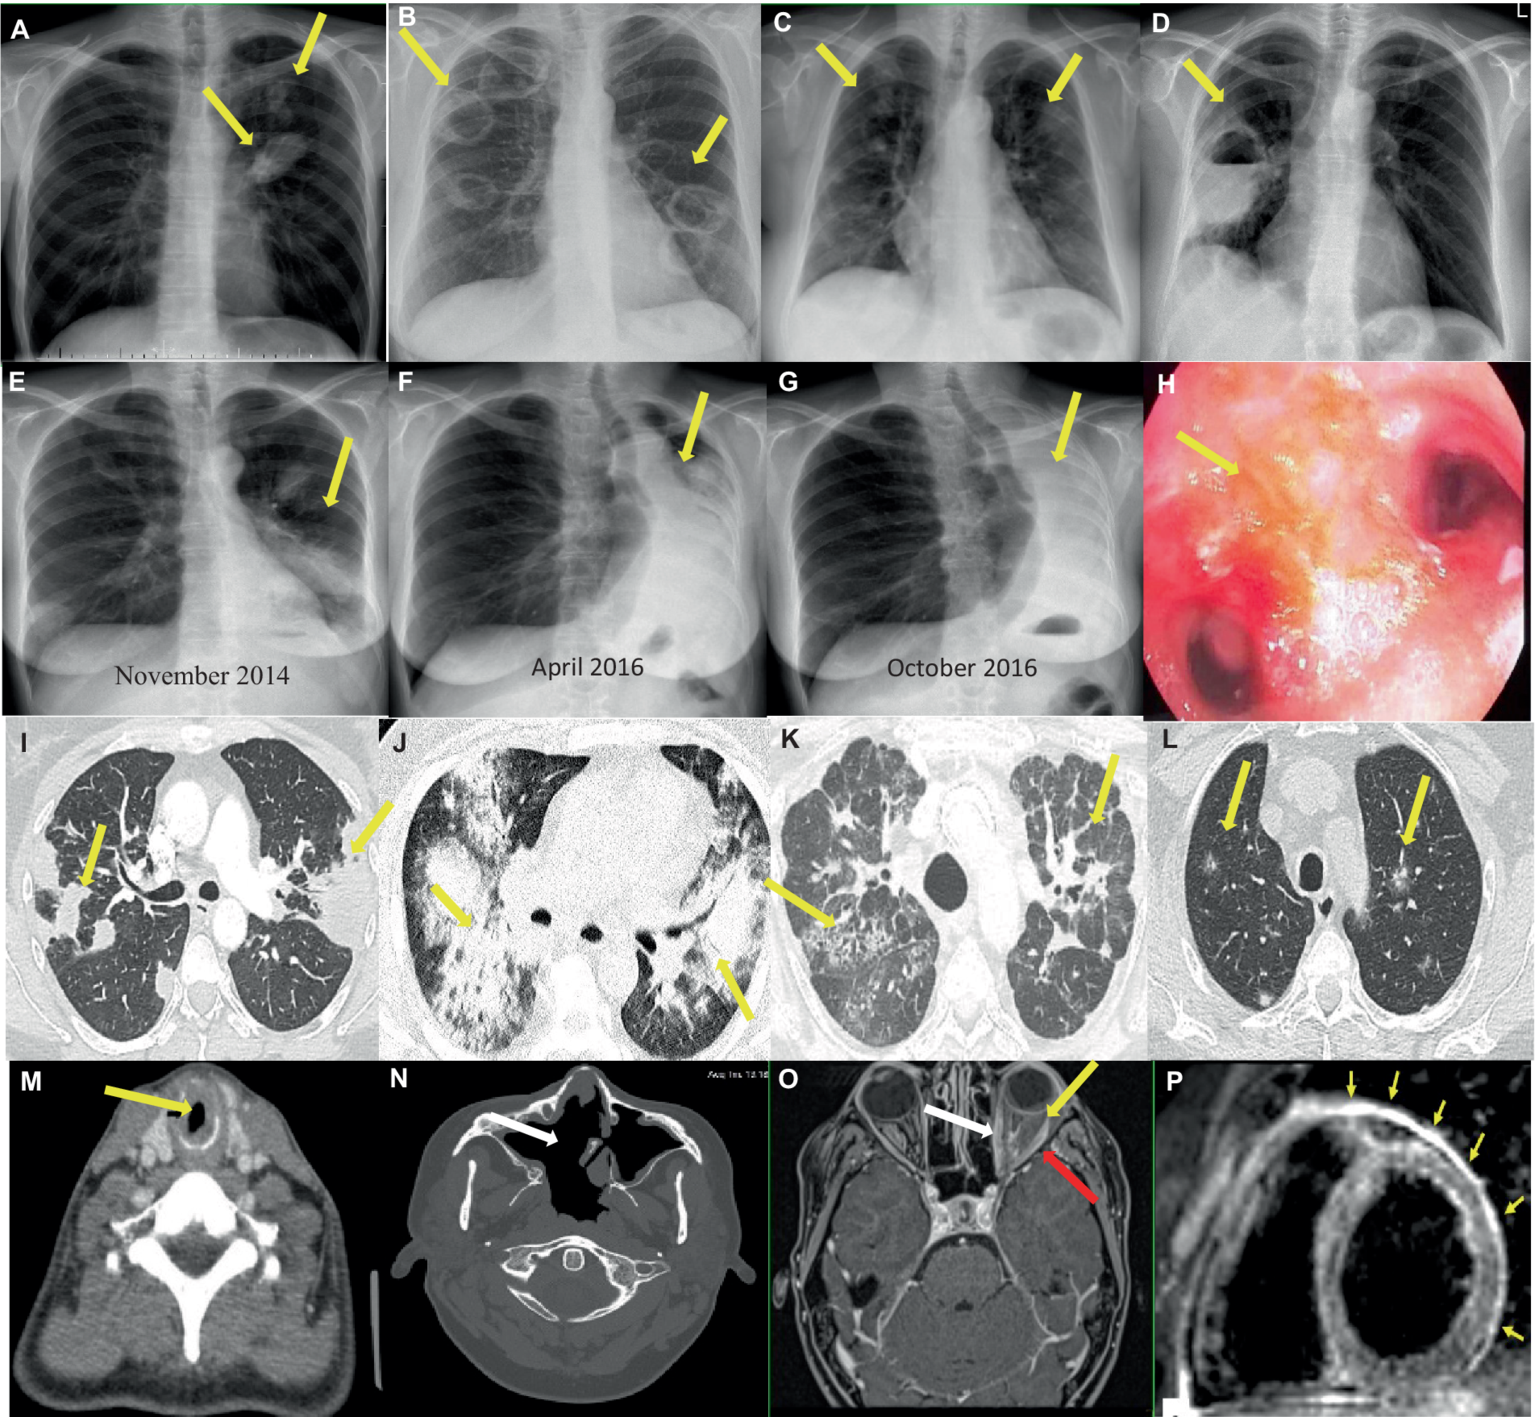

Selected imaging findings in patients with GPA shows Figure 3.

Figure 3

Imaging findings in patients with GPA. (A–G) Chest x-rays showing (A) Two nodular lesions (arrows) in the hilum and in the upper field of the left lung suspected initially for lung cancer. (B) Bilateral tumors with cavities (arrows) and (C) spread small lung nodules. (D) A thick-walled cavity with a fluid level in the right lung (arrow) suspected initially for lung abscess, and then for mycetoma. (E–G) Increasing obstruction of the left main bronchus (E,F), up to its complete closure and the formation of atelectasis of the left lung (arrows) (G) in the patient with tracheobronchial involvement. (H) Endoscopic image of endobronchial lesions (arrow). (I–L) Chest CT scans showing (I) Bilateral parenchymal infiltrations and consolidations (arrows) corresponding to OP pattern (axial image, lung window). (J) Bilateral ground-glass opacities in patient with diagnosed DAH (axial image, lung window). (K) Features of ILD (NSIP pattern) (arrows), which appeared after many years of suffering from vasculitis (axial image, lung window). (L) Bilateral small and randomly distributed nodules with “ground-glass” component (arrows) corresponding to GPA in histological examination (axial image, lung window). (M–N) Head and neck CT scans showing (M) SGS in the course of GPA - tracheal narrowing and thickening of the tracheal wall (arrow) (axial image). (N) A large single sinus cavity (arrow) as a result of the destructive granulomatous process of the nasal septum (axial image). (O–P) Contrast-enhanced MR showing (O) orbital mass in the left orbit (yellow arrow) with extraocular muscle enlargement (red arrow) and optic nerve sheath enhancement (white arrow) (T1-weighted, axial image). (P) Myocardial edema and thickened pericardium with hyperintense signal (arrows) corresponding to cardiac and pericardial involvement in the patient with GPA (black blood T2-weighted STIR images in short axis plane).